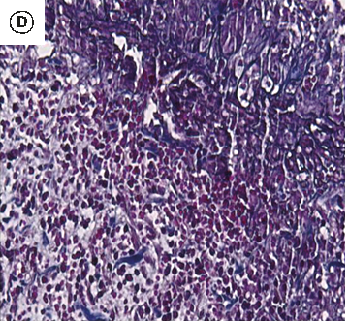

Figure 6

The Healing Effect of Aloe Vera Gel on Acetic Acid-Induced Ulcerative Colitis …